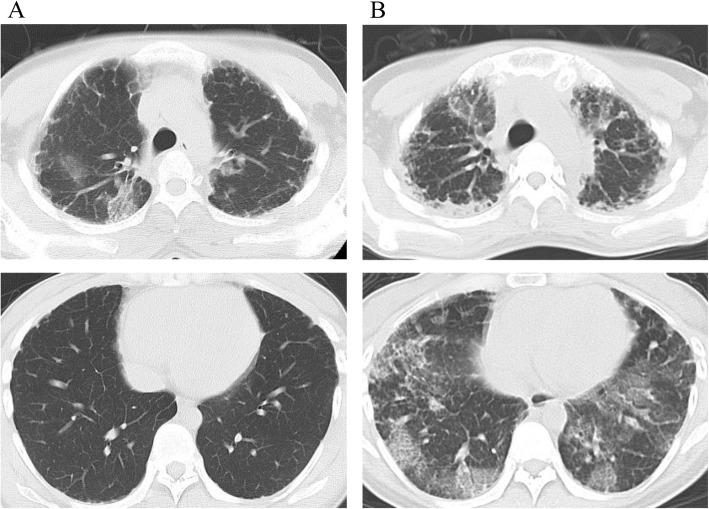

Idiopathic pleuroparenchymal fibroelastosis (IPPFE) is a rare lung disease that manifests as parenchymal fibrosis of the upper lung lobe and pleura. There have been no reports of IPPFE complicating pregnancy. Here, we report a case of IPPFE that deteriorated rapidly during pregnancy.

A 29-year-old woman presented with dyspnea and dry cough at 19 weeks of gestation. IPPFE with acute exacerbation was suspected on chest computed tomography (CT). Despite steroid treatment, her condition progressed. A cesarean section was performed at 28 weeks of gestation. On postoperative day 26, she underwent living-donor lung transplantation. She was discharged a year after transplantation.

特发性胸膜肺弹力纤维增生症(IPPFE)是一种罕见的肺部疾病,表现为肺上叶实质纤维化和胸膜纤维化。尚未有 IPPFE 合并妊娠的报道。本文报告了一例在妊娠期间迅速恶化的 IPPFE 病例。

一名 29 岁女性在妊娠 19 周时出现呼吸困难和干咳。胸部 CT 提示 IPPFE 伴急性加重。尽管给予了类固醇治疗,但病情仍在进展。患者在妊娠 28 周时行剖宫产术。术后第 26 天,她接受了活体供肺移植。移植 1 年后患者出院。